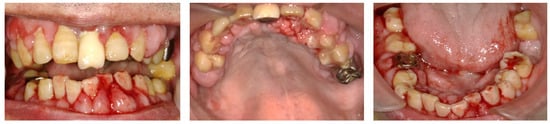

2. Case Presentation

2.1. Day 1: First Examination